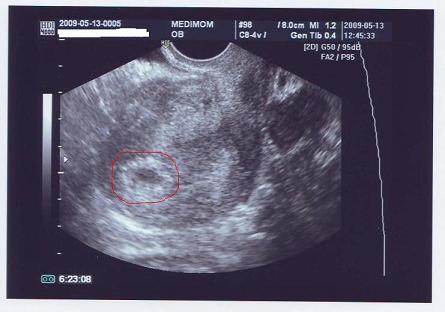

Editke - ne stresszelj! Tudom, mondani könnyű...de ezzel sztem is csak azt akarta mondani, h most okés minden, és ha esetleg 2 hét múlva is csak ekkora lenne a babuca (de nem ekkora lesz, mert nőni fog rendesen

), az lenne gond...mondjuk tényleg nem értem én sem, h minek riogat...

a petezsákjaidhoz! Én kettőt látok

a petezsákjaidhoz! Én kettőt látok